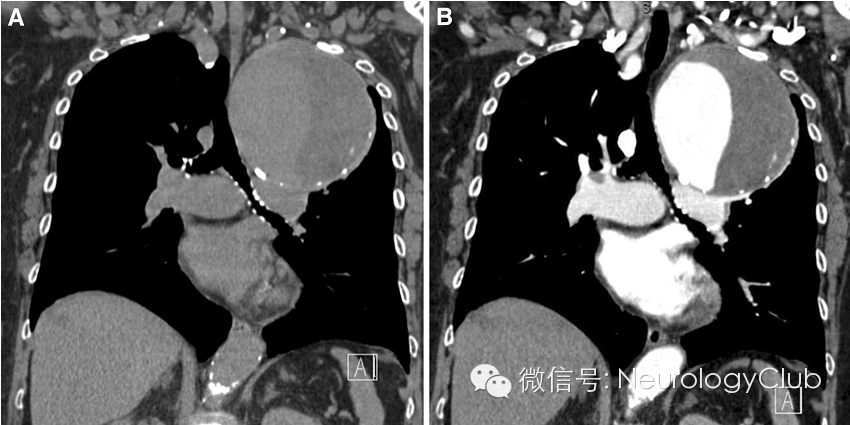

阴阳征表现为增强CT上,在扩张的卵圆形动脉截面内,可见半强化和半无强化区,形态酷似道教的阴阳符号。

阴阳征见于附壁血栓形成的真性和假性动脉瘤患者。动脉瘤为局限性或弥漫性的动脉管腔扩张,大于其正常直径的50%。假性动脉瘤指动脉管壁被撕裂或穿破,血液自此破口流出而被主动脉邻近的组织包裹而形成血肿,多由创伤所致。大动脉瘤和假性动脉瘤容易形成附壁血栓,因此血流仅充盈部分管腔。阴阳征中,造影剂充盈增强的部分代表通畅的管腔,而无造影剂充盈的部分则代表附壁血栓的形成。

病例5:胸主动脉瘤患者